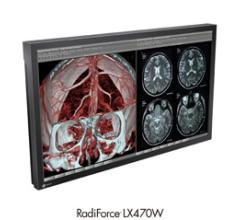

EIZO GmbH, Display Technologies expanded its portfolio of medical surgical monitors by announcing the RadiForce LX470W, a 2 megapixel widescreen monitor.